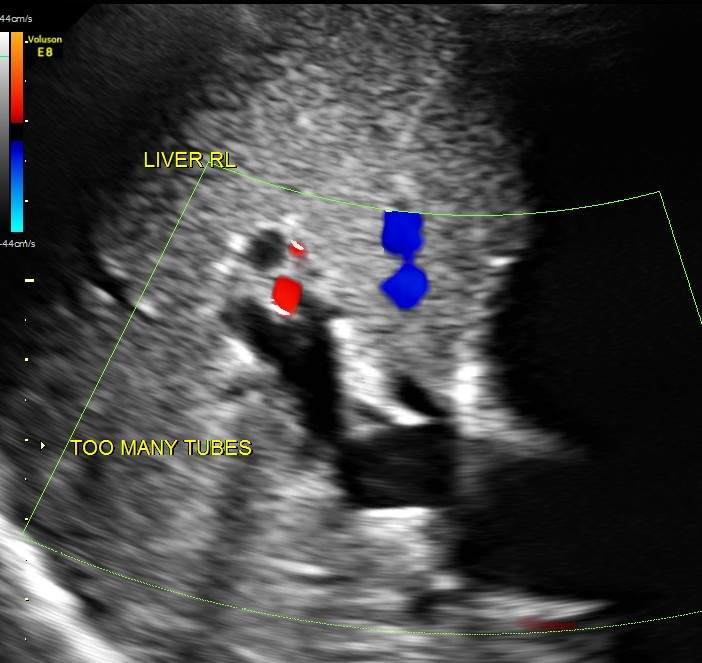

Courvoisier’s law (or Courvoisier syndrome, or Courvoisier’s sign or Courvoisier-Terrier’s sign) states that in the presence of an enlarged gallbladder which is nontender and accompanied with mild jaundice, the cause is unlikely to be gallstones. Usually, the term is used to describe the physical examination finding of the right-upper quadrant of the abdomen. This sign implicated possible malignancy of the gall bladder or pancreas and the swelling is unlikely due to gallstones.

This was a 55 year old man with history of jaundice and upper abdominal pain .